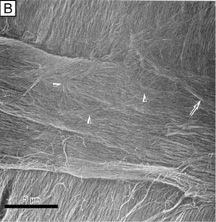

Collagen type VI is the third most common type of collagen in the corneal stroma, but is unique in that it is only able to aggregate into repeating tetramers of type VI molecules. Thus, it forms only 10 to 15 nm diameter, beaded (20 × 30 nm diameter ovals with a periodicity of 100 nm), nonbanded filaments (Fig. 11A). Functionally, it acts as a bridging filament that binds corneal lamellae together where they cross each other (Fig. 11B, C). Along with fibril-associated collagens with interrupted triple helices (FACIT collagens, type XII and XIV collagen molecules), it also bridges intralamellar fibrils together (Fig. 11D).57,58 Overall, this three-dimensional, supramolecular scaffold created by human corneal stromal collagens results in a one-dimensional ordered (∼22 nm diameter collagen fibrils; ∼ 40 nm interfibrillar spaces × random directionality) 12-μm thick acellular Bowman's layer (Figs. 12A and 13A) and a three-dimensionally-ordered (∼25 nm diameter collagen fibrils; ∼ 40 interfibrillar spaces × parallel directionality) series of successive stacks of lamellae in the cellular stroma measuring in the center of cornea around 450 μm in thickness.59–61

Fig. 11. (A) Diagram of a type VI collagen molecule and how it assembles into filaments by aggregating into repeating tetramers of type VI molecules (periodicity of 100 nm). (B) Low magnification (6,200×) SEM showing bundles of collagen filaments extending between lamellae (arrow) and a loose meshwork of collagen filaments on the posterior surface of a corneal lamellae where an adjacent lamellae crosses it (arrowheads). Bar = 5 μm. (From Komai Y, et al. The three-dimensional organization of collagen fibrils in the human cornea and sclera. Invest Ophthalmol Vis Sci 32:2244, 1991.) (C) High magnification (115,000×) quick-freeze, deep-etched electron micrograph showing a loose meshwork of interlamellar beaded filaments with a periodicity of 100 nm (thick arrows) which appear to bind to collagen fibrils (long arrow) by their beads (arrowhead) and join fibrils from separate lamellae together. Bar = 0.2 μm. (D) Very high magnification (185,000×) quick-freeze, deep-etched electron micrograph of intralamellar collagen fibrils (long arrows) with beaded filaments (thick arrows) crisscrossing between fibrils and projecting three finger-like structures, which both appear to function in joining neighboring fibrils together. Bar = 0.1 μm. (C and D are from Hirsch M, et al. Three-dimensional supramolecular organization of the extracellular matrix in human and rabbit corneal stroma, as revealed by ultrarapid-freezing and deep-etching methods. Exp Eye Res 72:123, 2001.)